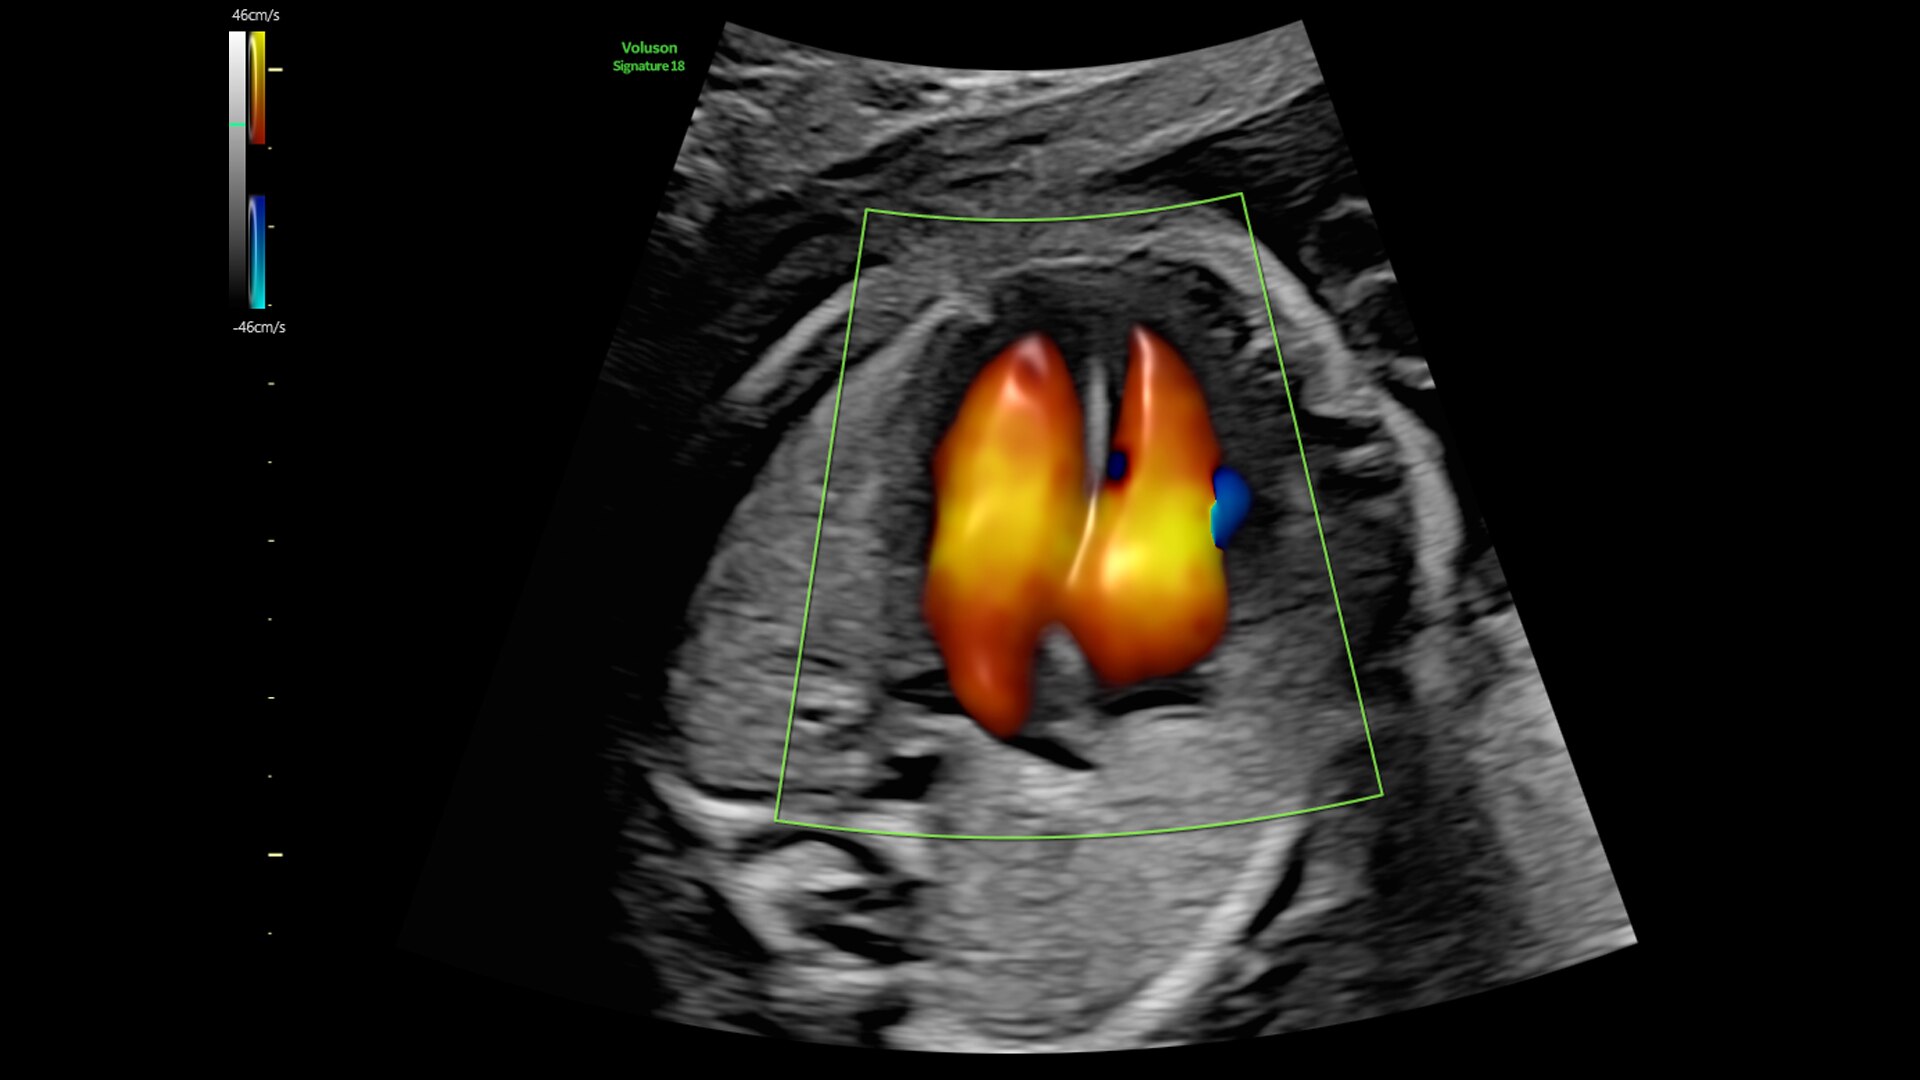

Radiantflow

Fast, easy 3D-like blood flow visualization

Next level color Doppler delivers exceptional sensitivity for easy, fast visualization of blood flow, revealing even the tiniest vessels.

3-radiantflow-clinical-image